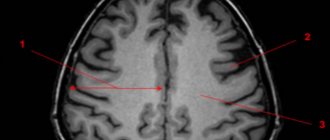

Основным методом ее диагностики является МРТ. На снимках арахноидальные изменения ликворокистозного характера выглядят как образования темного цвета, с четко ограниченными контурами, чаще всего округлой формы.